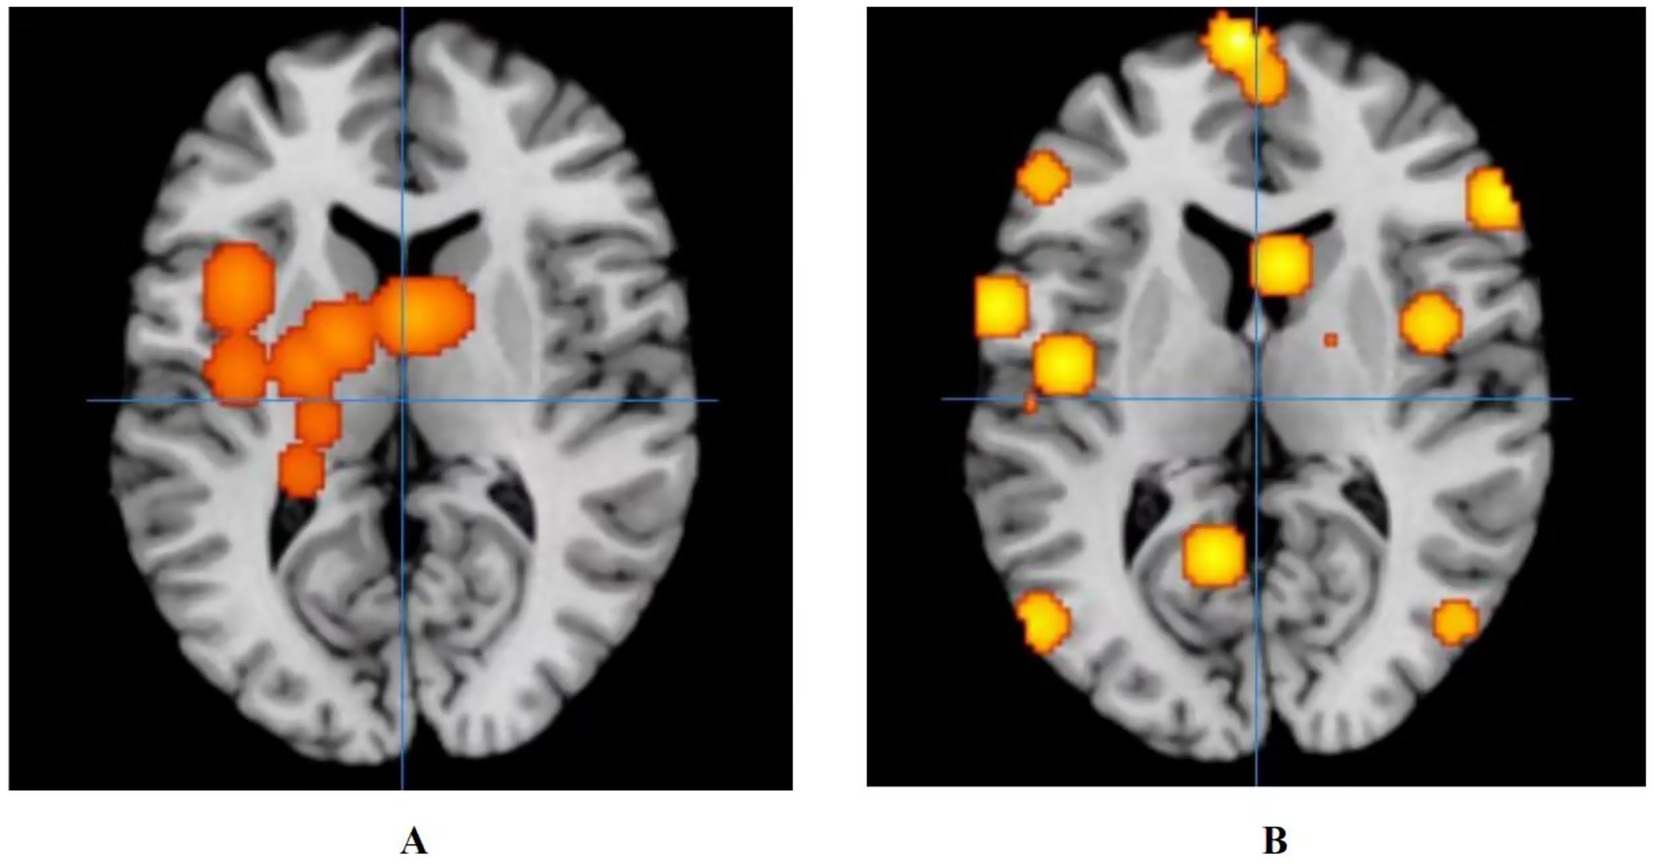

3.4.3 Neuroimaging results after the control group’s treatment on ANSLBP

The results showed that the control group’s treatment for ANSLBP activated over eight clusters, predominantly located in the sub-lobar regions of the left cerebrum, including the insula, lentiform nucleus, thalamus, caudate, and hippocampus. Only the caudate in the right cerebrum showed activation. It was clear that most of the activated clusters were in the sub-lobar area. Additionally, the ALE values ranged from 0.0009 to 0.001, with the insula in the left cerebrum displaying the highest activation, specifically centered at x = −40, y = 6, z = 18 (ALE = 0.0014, p < 0.001, Z = 4.05) (Figure 4A). In summary, the results indicate that significant brain activation occurs primarily in the sub-lobar region, with the left insula showing the highest activation, which may be central to the neurophysiological response to ANSLBP treatment.

Figure 4. Activation of fMRI signals in cortical and subcortical structures in the control group. (A) Activation of brain regions in patients with ANSLBP after receiving treatment in control group; (B) Activation of brain regions in patients with CNSLBP after receiving treatment in control group.

3.4.4 Neuroimaging results after the control group’s treatment on CNSLBP

Long-term control group’s regulates wider areas, such as the limbic lobe (Brodmann area 40; peak MNI coordinates: −50, −28, 52; peak SDM-Z (Seed-based d Mapping): 3.597; p < 0.001), the parietal lobe (Brodmann area 36; peak MNI coordinates: −50, −34, −16; peak SDM-Z: 3.597; p < 0.001), the frontal lobe (Brodmann area 6; peak MNI coordinates: 44, 6, 30; peak SDM-Z: 3.597; p < 0.001), the temporal lobe (Brodmann area 22; peak MNI coordinates: −66, −42, 18; peak SDM-Z: 3.597; p < 0.001), the sub-lobar (Caudate Body; peak MNI coordinates: 18, −4, 16; peak SDM-Z: 3.597; p < 0.001), and the occipital lobe (Brodmann area 37; peak MNI coordinates: −52, −72, 4; peak SDM-Z: 3.597; p < 0.001) (Figure 4B).